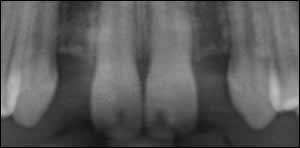

Fig 1: A teenager presented with congenitally missing maxillary lateral incisors.

Fig 2: Pre-Operative radiographs revealed insufficient space for conventional size implants.